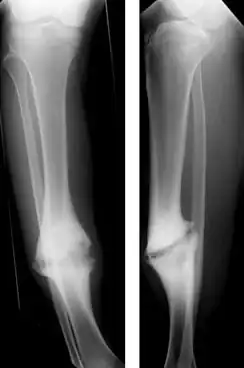

Pseudoartrose (grego antigo para falsa articulação) é uma séria complicação de uma fratura óssea na qual o osso nunca se regenera. Uma cicatriz de tecido fibroso se forma no meio do osso. Sem tratamento resulta em deformidade e prejuízo permanente da função, como por exemplo uma perna torta e incapaz de suportar peso se a pseudoartrose é no fêmur ou na tíbia. O tratamento é cirúrgico e a recuperação demora muitos meses.

Embora não seja tão conhecida da população, é um problema bastante comum e alvo de inúmeros estudos na área científica, entre eles, por exemplo, a deficiência femoral proximal, que é dividida em vários tipos. No Tipo A de deficiência femoral proximal, segundo a classificação de Aitken, verificou-se que o osso se encontra acentuadamente angulado, podendo haver uma pseudoartrose. No Tipo B da classificação de Boyd (tíbia - displásica), ocorre com um encurvamento anterior. A fratura ocorre espontaneamente ou após um trauma mínimo antes dos dois anos de idade. As extremidades ósseas no foco da pseudoartrose são atróficas, lembrando uma ampulheta. Podem estar associadas a manchas café-com-leite, parecidas com as de uma neurofibromatose. Em geral, a fíbula também está comprometida. Este tipo é o mais comum e também o de prognóstico menos favorável que em outros tipos de deformidade congênita, entre os quais se encontra o pé torto, este com bom prognóstico.

O diagnóstico geralmente é feito nas consultas de seguimento seis a oito semanas depois da fratura com raio X e exame físico. Dor, fragilidade e incapacidade funcional indicam que o osso não se consolidou bem.[2] Em caso de dúvida a consolidação inadequada é melhor vista com tomografia computadorizada ou com radiografia dos movimentos disfuncionais (stress Rx).